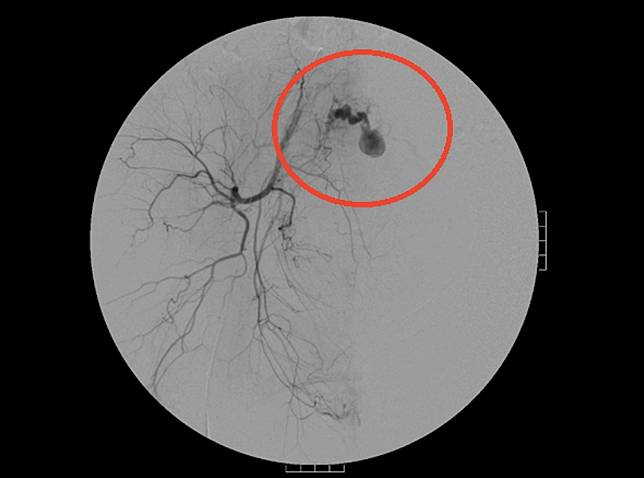

▲國泰醫院收治罕見個案,剖腹產雙胞胎,產後4周卻發生大出血。(照/國泰醫院提供)

王小姐的大出血狀況特殊,每一次出血都有1000到2000cc之多,儘管醫師給予藥物治療,清掉血塊,報告也都正常,顯示沒有胎盤殘餘,但只要藥效一過隨即又發生出血,前後折騰3次,進一步使用顯影劑檢查後,才發現是子宮內右側血管瘤造成的大出血,栓塞治療才解除危機。

蔡明松說,處置產後出血得視引起產後出血的原因而定,臨床上會先以藥物治療,若藥物治療無效時則採手術處理,方式包括B-Lynch縫合術、子宮切除術或經導管動脈栓塞術,其中經導管動脈栓塞術是利用血管X光攝影方式,將微導管沿股動脈尋找至出血點,再以一種栓塞物打入動脈內,或以氣球將供應子宮血液的動脈塞住,幫助產婦止血,子宮也得以保留。